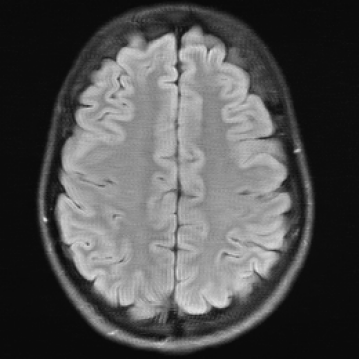

The reconstructions in Figure 5 were obtained by the application of E2E-VarNet, Figure 5 (b)(c)(e)(f), and XPDNet, Figure 5 (a)(d), to accelerated data with random masks (acceleration factor between 1 to 5) in the frequency domain.

Refer to caption

(a) (27.8, 0.78, 0.14)

(b) (29.6, 0.85, 0.14)

(c) (32.3, 0.92, 0.04)

(d) (29.5, 0.84, 0.12)

(e) (29.6, 0.86, 0.12)

(f) (33.0, 0.94, 0.04)

Figure 5: Reconstruction outputs of accelerated FLAIR MRI data from the algorithms Xpdnet(a)(d) and E2varnet (b)(c)(e)(f). The bottom images (d)-(f) are judged by PSNR/SSIM/LPIPS as better reconstructions than the respective image above them (a)-(c), although visually they clearly have worse quality.

FR-IQA mismatch

We can see in Figure 5 that the visual quality of the obtained images does not correspond to the numbers provided by PSNR/SSIM/LPIPS. This is not surprising as some challenges with SSIM as a performance metric have already been discussed in the official results paper of the challenge (citep \@BBN(Muckley et al., 2021a)) and small artefacts/wrong lesions have been shown. Here, we complement with examples where the visual results clearly ask for a different judgement even in a non local manner. In particular, the bottom images in Figure 5 show stronger artefacts and loss of information in comparison to the images on top. In addition, the degraded images (e) (f) do hold quite higher numbers in comparison to (a) which is nearly noise-free.